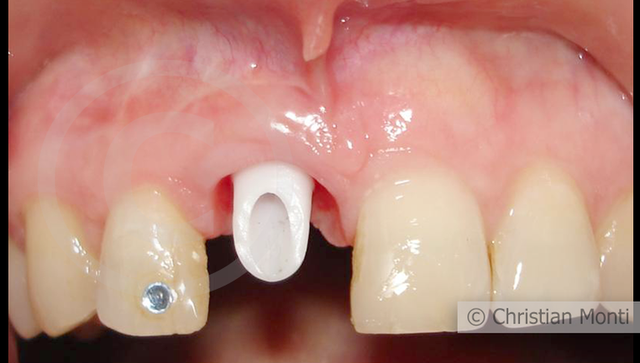

EDENTULIA SINGOLA

Impianto in sostituzione di un incisivo superiore